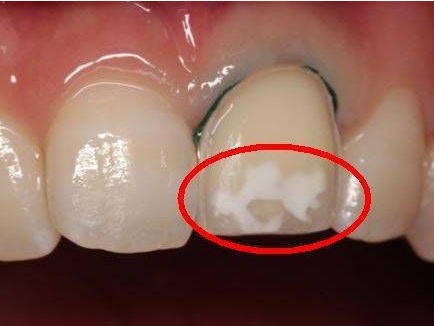

有的家长说小朋友的牙齿从长出来就有“白点”,咨询医生后被告知为“牙釉质钙化不全”,家长说那我们从现在开始吃钙片补钙可以嘛,其实不然,牙齿各部位的组织都是高度钙化的物质。其中90%是磷酸钙,所以说钙是牙齿发育过程中的重要元素。如果牙齿在钙化阶段(即未萌之前)得到充足的钙,对牙齿的发育是有利的。但有些牙齿萌出以后,发现发育不好,故有些人认为多吃些钙片就能补救牙齿的发育,这是不对的。因为牙齿萌出之后,也就意味着钙化结束。这就好比建造一幢楼房,竣工后对楼房的质量不满意,再加钢筋水泥也是无济于事的,这也和牙齿一样,外形虽可修饰,但程度有限,对牙齿来说,已经钙化的主体,是不能通过萌出后的代谢进行重建。